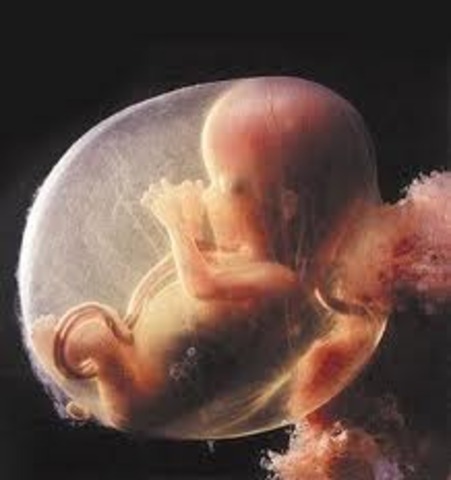

Week 10

Your baby has small indentations on his legs, and his tiny arms even have elbows that bend. Inside that little mouth, tiny buds of baby teeth are forming under the gums. His stomach and kidneys are kicking into gear, producing digestive juices and urine, and if it's a boy, his testes are making testosterone.